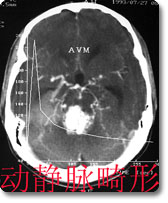

中枢神经影像诊断是本科室的特色、强项诊断之一,尤其是现代影像学诊断,如CT、MRI等,是西南地区最早开展此项工作的单位,积累了丰富的临床经验,有较高的诊断水平。如对脑肿瘤的影像学表现和肿瘤分子生物学基础的对照研究、脑血管病的诊断和介入治疗等在国内处于领先地位。 |